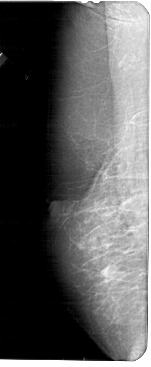

A_1661_1.RIGHT_MLO

RIGHT_MLO LINES 5221 PIXELS_PER_LINE 2431 BITS_PER_PIXEL 12 RESOLUTION 43.5 OVERLAY

FILE: A_1661_1.RIGHT_MLO.OVERLAY

TOTAL_ABNORMALITIES 1

ABNORMALITY 1

LESION_TYPE MASS SHAPE ASYMMETRIC_BREAST_TISSUE MARGINS ILL_DEFINED

ASSESSMENT 4

SUBTLETY 5

PATHOLOGY MALIGNANT

TOTAL_OUTLINES 1

BOUNDARY